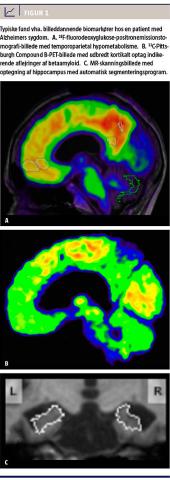

spinalvæsken (CSV) og øget kortikalt optag af positronemissionstomografi (PET)-ligander med bindingspotentiale til aβ (f.eks. 11C-Pittsburg-compound B og forskellige 18F-mærkede ligander), der begge afspejler øget kortikal aβ-aflejring, og 2) reduceret kortikal 18F-fluorodeoxyglukose (FDG)-PET-aktivitet, forhøjet totaltau (t-tau) og fosforyleret tau (p-tau) i CSV samt CT- eller MR-skanningsverificeret atrofi, der afspejler neurodegeneration (Figur 1). I 2010 [7] (med opdateringer i 2013 [8]) blev en samlet model for ændringer i disse biomarkører publiceret. Således formodes nedsat aβ i CSV at være den tidligste ændring efterfulgt af øget kortikalt optag af PET-ligander med affinitet til aβ derefter stigning i t-tau i CSV efterfulgt af atrofi målt med MR-skanning og synaptisk dysfunktion målt med 18F-FDG-PET. I dette stadie opstår de første milde kognitive symptomer [8]. Der vil være betydelig tidsmæssigt overlap mellem ændringerne, og ændringerne i biomarkørerne er ikke velafgrænsede faser, der skal løbe til ende, før næste fase begynder, og kan heller ikke sikkert tilskrives en årsagssammenhæng. Aflejring af aβ begynder formentligt 10-15 år før symptomdebut [9] og er en nødvendig, men ikke tilstrækkelig årsag til udviklingen af AS.

Ved 18F-FDG-PET måles glukosemetabolismen, som er en markør for synaptisk aktivitet. Ved AS ses der typisk temporoparietal kortikal hypometabolisme

(Figur 1), mens der ved frontotemporal demens (FTD) ses hypometabolisme frontalt og temporalt. Denne forskel gør 18F-FDG-PET til et nyttigt diagnostisk redskab til separering af FTD med amnestiske symptomer fra AS med frontale træk. Atypiske, nonamnestiske tilfælde af AS såsom posterior kortikal atrofi og logopenisk afasi vil tillige have særegne mønstre med hhv. posterior hypometabolisme og temporoparietal venstresidig hypometabolisme. Ved Lewy body-demens (LBD) er occipital hypometabolisme, specielt i visuel cortex, hyppigere, men kan også forekomme ved AS. Skanningen kan bedømmes visuelt af en nuklearmedicinsk ekspert, men også med særligt software, der typisk er leveret med skanneren og gør det muligt at kvantificere glukoseme-